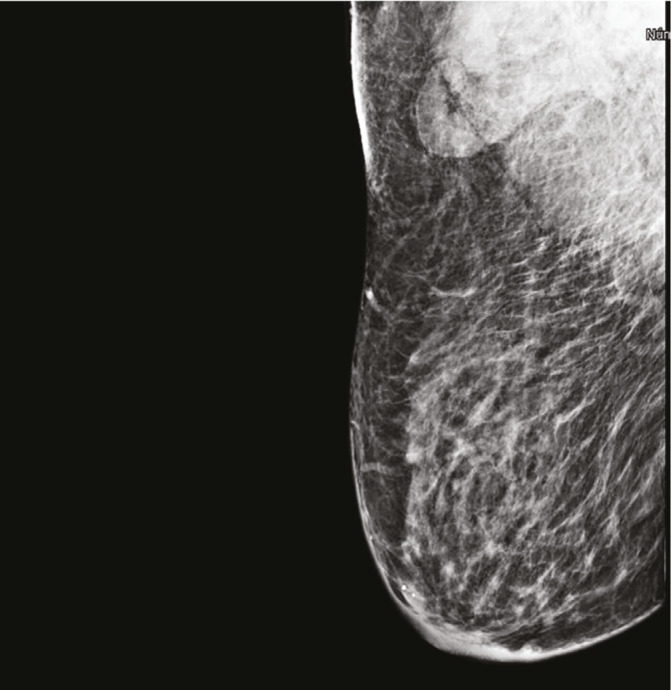

Breast lymphedema is a common but underdiagnosed condition that affects the quality of life of patients. It may be caused by any pathology that disrupts lymphatic drainage in the breast. We present the case of a woman with axillary lymph node tuberculous infection with breast edema, clinically and radiographically indistinguishable from tuberculous mastitis. After six months of comprehensive antituberculosis pharmacological treatment, the persistence of breast edema required repeating diagnostic tests searching for malignancy, all of which were negative. Rehabilitation treatment with complex physical therapy improved the patient's clinical and symptomatic condition. Clinical suspicion of secondary lymphedema is crucial to avoid unnecessary diagnostic procedures and ensure adequate and timely treatment.

Abstract Image